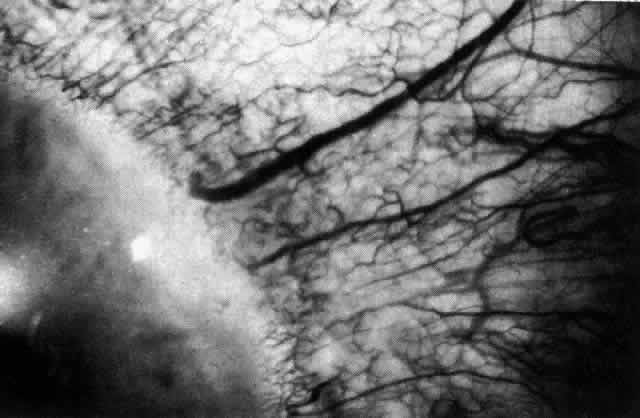

In this relatively benign form of scleral inflammation, the fluorescein

angiogram reveals a rapid flow pattern in which the transit time of the

dye is very rapid (as in episcleritis) (Figs. 32 and 33). Subtle changes occur in the capillary network, and abnormal leaking

vessels appear after prolonged inflammation. These changes do not disappear

after the inflammation subsides or is treated (see Fig. 31).  Fig. 32. Diffuse anterior scleritis associated with corneal edema. The limbal vessels

Fig. 33. Fluorescein angiogram of patient in Figure 32 four seconds after the appearance of the dye. This is a very rapid transit

time. All the limbal capillaries are completely full, and all the

major episcleral vessels contain fluorescein. Note that the very large

vessel is a vein, and the narrow vessel below it is an artery. The deep

vessels are distorted, and some are abnormal in configuration. Fig. 33. Fluorescein angiogram of patient in Figure 32 four seconds after the appearance of the dye. This is a very rapid transit

time. All the limbal capillaries are completely full, and all the

major episcleral vessels contain fluorescein. Note that the very large

vessel is a vein, and the narrow vessel below it is an artery. The deep

vessels are distorted, and some are abnormal in configuration.

|